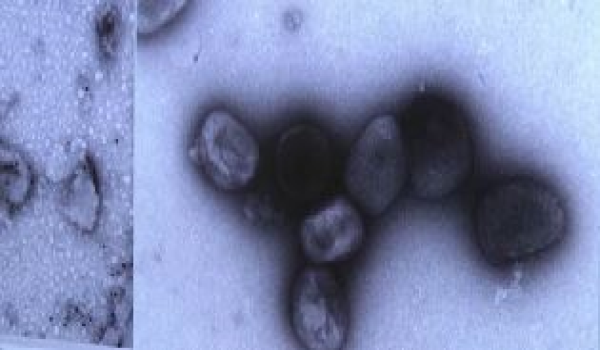

(Foto hiasan/Fail)